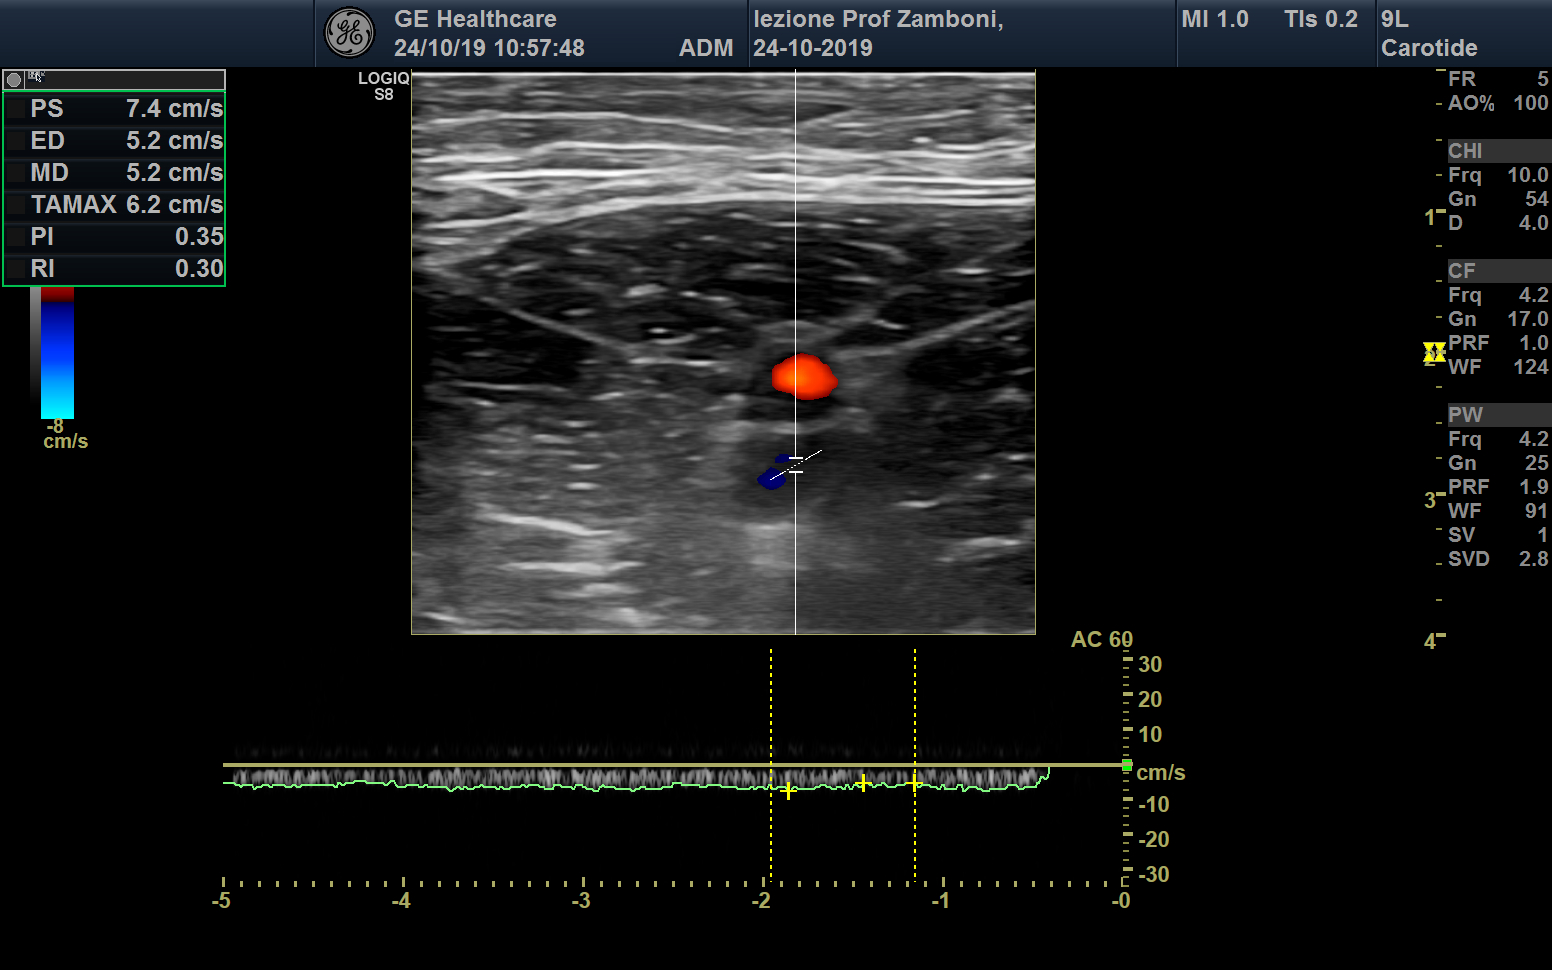

PW V. Femorale

JPEG image icon PW V. Femorale.jpg — JPEG image, 552 kB (566114 bytes)